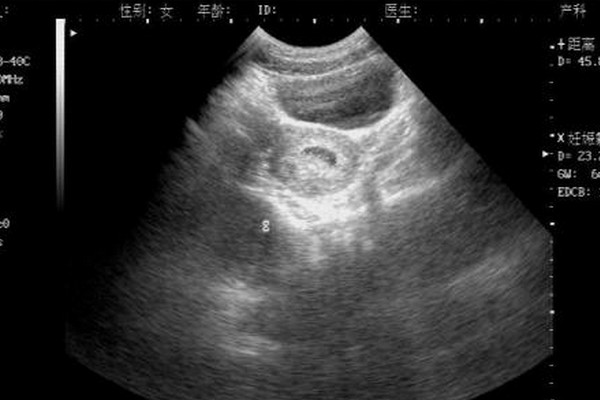

孕7周孕囊過大胎芽偏小易胎停流產,背後真相大盤點

孕7周孕囊大小標準值應該在2.5到3cm之間,而孕囊太大胎芽偏小屬於胚胎髮育不良的一種B超表現,這種大孕囊是不正常的,所以容易胎停流產。這與胚胎質量不好、母體內分泌紊亂、凝血功能異常、免疫因素等有一定的關係,相當一部分大孕囊患者在檢查後1-... 全文